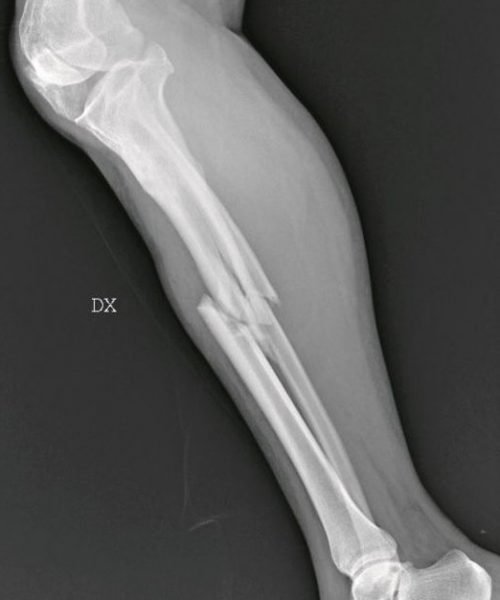

Σπασμένη κνήμη

Όπως σημειώνει η χειρουργός, καθημερινά καλούνται να αντιμετωπίσουν «σπασμένα οστά σε μύτη, χέρια, πόδια, πληγές από μαχαιριές, εγκαύματα, μελανιές και άλλα σημάδια στραγγαλισμού», ενώ σημειώνει πως έχει δεχθεί ασθενή ακόμη και με μαχαίρι στην πλάτη, που όμως το περιστατικό δηλώθηκε ως «ατύχημα» στο νοσοκομείο.

Σύμφωνα με την Βανταντόρι, στις ακτινογραφίες αντικατοπτρίζεται η καθημερινή φρίκη που αντιμετωπίζει με τους συναδέλφους της στα «Επείγοντα». «Συχνά οι τραυματισμένες γυναίκες δεν έχουν τη δύναμη να πουν τι τους έχει συμβεί, αλλά τα σώματά τους και τα τραύματά τους μιλούν από μόνα τους», σημειώνει.

«Όλα αυτά τα χρόνια έχω δει χιλιάδες ακτινογραφίες γυναικών με κάθε είδους τραύματα, ακόμη και πολύ σοβαρά. Πολλές από αυτές τις κακοποιημένες γυναίκες αρνήθηκαν ότι τα τραύματά τους προκλήθηκαν από τους συζύγους ή άλλα μέλη της οικογένειάς τους. Η άρνησή τους σχετίζεται με συναισθήματα όπως φόβος, ντροπή, αγωνία για την τύχη των παιδιών τους ή και για τη ζωή τους ακόμη», σημειώνει η γιατρός.